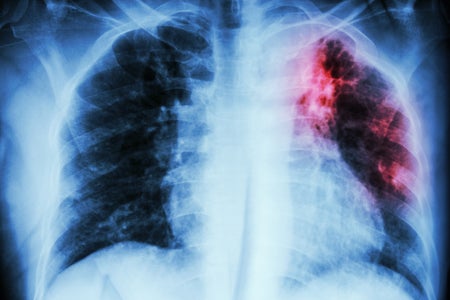

Five Interventions for Treating Multidrug-Resistant TB

The FDA has approved a drug combination that could be a game changer. We should make sure its use is equitable and sustainable